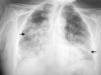

Pancreatitis y colostasis disociada agudas: manifestación inusual en la infección por Legionella pneumophila

Pancreatitis and dissociated cholestasis: An unusual manifestation in Legionella pneumophila induced-infections